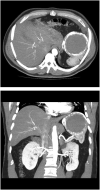

Case presentation: A 56 year old male patient, presented with symptoms of pain in the left side of middle back and discomfort in the left hypochondrium for few months. His physical examination was unremarkable. The abdominal Ultrasound and contrast-enhanced Computed tomography showed a large splenic cyst occupying most of the splenic parenchyma. Echinococcus multilocularis antibody test was negative. The differential diagnosis of this case included non-parasitic splenic cysts. The patient underwent elective exploratory laparoscopy which was converted to laparotomy with total splenectomy. Histopathological examination of the specimen revealed a splenic pseudocyst.

Clinical discussion: The splenic cyst in this case was symptomatic due to its large size. It was hard to elicit an etiology as there was no history of abdominal trauma, infection, or degenerative disease. The main factors in selecting either conservative or radical surgical approach for such cases are the cyst location, cyst size, and the residual splenic parenchyma.